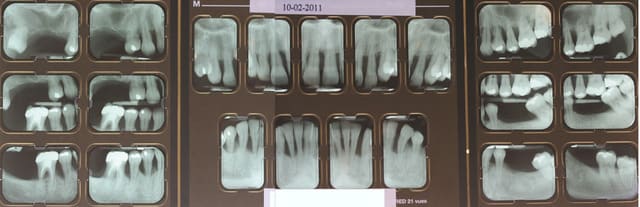

la patiente est très jolie, elle a 30 ans, a consulté deux ou trois dentiste en l'espace de 10 ans, le dernier détartrage date il y a trois ans et il n'a pas été terminée apparemment car la patiente avait trop de douleurs, et aujourd'hui elle est adressée par un hôpital parisien qui devait lui poser des implants et qui devant la panoramique a renoncé sans pour autant la diriger correctement.

PS : ce qui me donne pas mal d'espoir dans ce cas-là, c'est tout de même les nombreuses lésions angulaires, qui vont bien accepter la pose de biomatériaux.

Quelles sont dans le cas que tu nous présentes les lésions angulaires que tu juges avoir un bon potentiel régénératif ? Pourquoi ?

Principalement les lésions en forme de cuvettes que l'on retrouve en secteur 2 et 4. Cette forme de lésions permet une meilleure tenue du biomatériau et permet un afflux sanguin perpendiculairement à la paroi. C'est le même principe que la cicatrisation d'une alvéole intacte sans paroi manquante.

Théoriquement après cica, on peux esperer une réossification au mieux jusqu'à la limite haute de la cuvette.

on est clairement devant une parodontite agressive généralisée avec comme facteur de risque le Tabac et un facteur aggravant l'occlusion ...

- Full mouth en 2 séances espacées de 24 à 48h selon le protocole de Qyrnen, antibiothérapie AMX / metro pdt 10j à commencer apres avoir desorganiser le biofilm c'est à dire à la fin de la full mouth

Lambeau d'assainissement des poches Sup à 6mm avec BOP